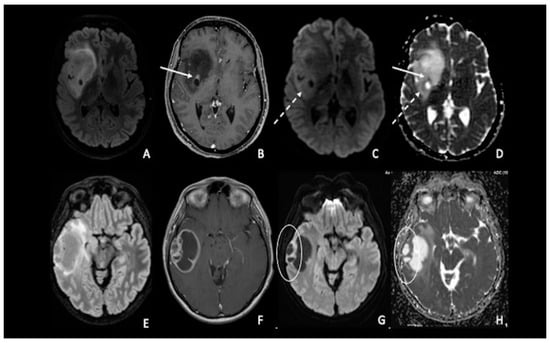

4. Lymphomas

7. Metastasis